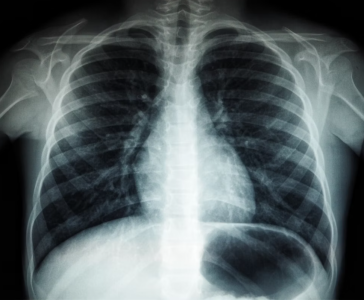

Tuberculosis is caused by a bacterium called Mycobacterium tuberculosis. It primarily attacks the lungs, but it can also affect other parts of the body, like the kidneys, spine, or brain.